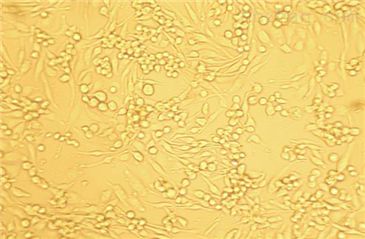

细胞生长:贴壁生长

细胞形态:上皮样

细胞数量:1×106个细胞数

细胞纯度:94%

细胞活力:90%(ViabilitybyTrypanBlueExclusion)